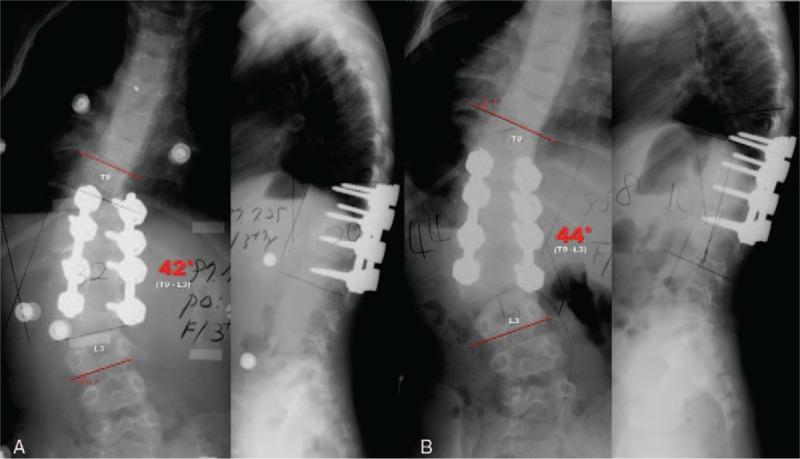

We report an 11-year follow-up of revision surgery for fractional curve progression after combined anterior and posterior fusion without hemivertebra resection using pedicle screw fixation (PSF) in congenital kyphoscoliosis at age 4 years (a total 18-year follow-up). A T12 hemivertebra was documented in a 4-year-old girl and was treated by combined anterior and posterior fusion in two stages with PSF. The fusion mass was maintained but the distal compensatory curve progressed during the follow-up period. The patient underwent a posterior vertebral column resection (PVCR) with extended posterior fusion at the age of 11, 7 years after initial surgery.

我们报告了一例4岁先天性脊柱后凸侧凸患者在未行半椎体切除的情况下采用椎弓根螺钉固定(PSF)进行前后联合融合术后因分节段曲线进展而进行翻修手术的11年随访情况(总计18年随访)。一名4岁女孩被诊断为T12半椎体,分两阶段采用PSF进行前后联合融合治疗。随访期间融合块保持稳定,但远端代偿性曲线进展。患者在初次手术后7年,即11岁时接受了后路脊柱椎体切除术(PVCR)及扩大后路融合术。